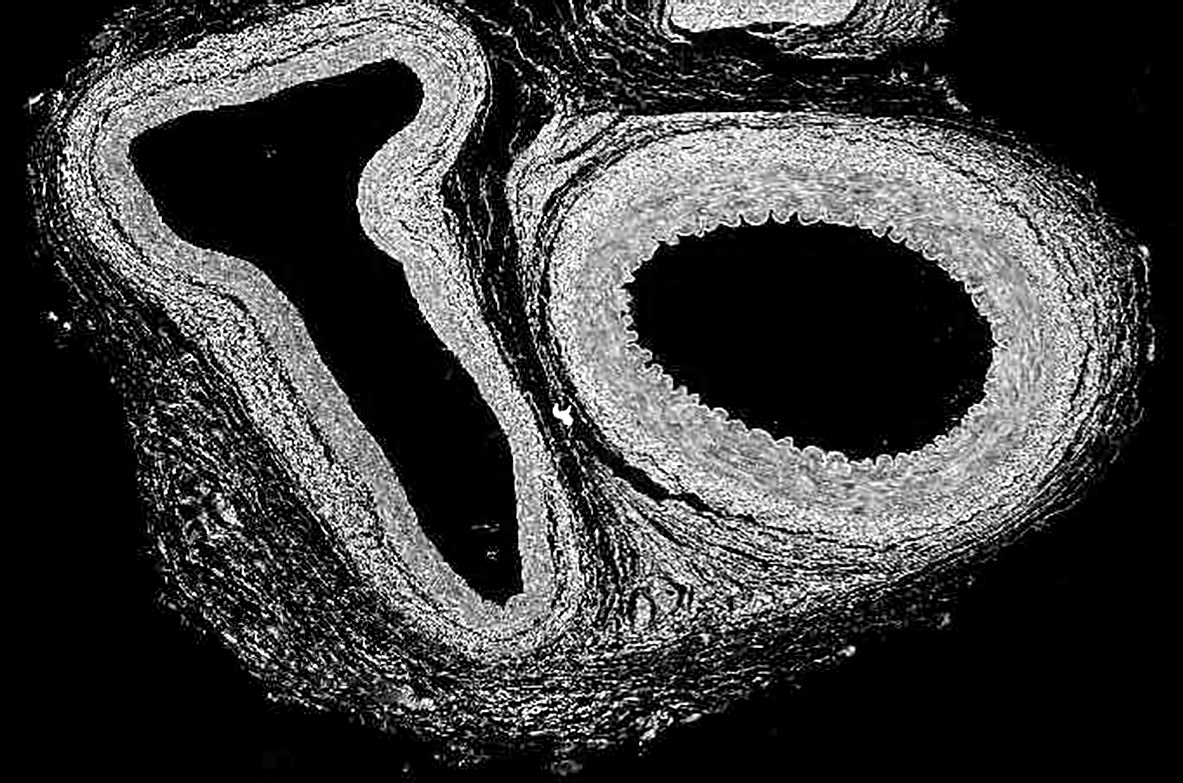

- The micrograph shows tissue with two major blood vessels.

(a) Label an artery on the diagram. [1]

(b) Distinguish between the structure of arteries and veins. [2]

(c) Suggest a reason that capillaries are not visible in the micrograph. [1]